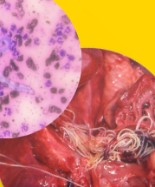

การวินิจฉัยโรค

การวินิจฉัยโรคมะเร็งเม็ดเลือดขาวในแมวต้องอาศัยการตรวจเลือดโดยเฉพาะ ได้แก่

- การตรวจหาเชื้อไวรัส FeLV โดยใช้ชุดตรวจแบบรวดเร็ว (Snap Test)

- การตรวจเลือด CBC เพื่อดูความผิดปกติของเม็ดเลือดแดง เม็ดเลือดขาว และเกล็ดเลือด

- การตรวจทางชีวเคมีในเลือด เพื่อประเมินการทำงานของอวัยวะต่างๆ

- การตรวจเพิ่มเติม เช่น การตรวจน้ำในช่องอก, การเอ็กซ์เรย์ หรืออัลตราซาวด์